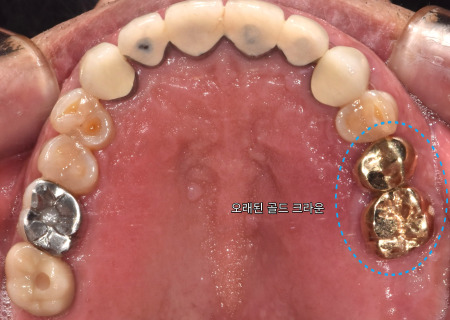

사진처럼 빠진 크라운을

입 속에 끼워 놓으신 채

오셨는데요.

금속 기공물은

머리 부분을 보호하는

기능을 하는 좋은 재료인데요.

접착제로 붙이는

방식이다 보니

지금처럼 빠지는 경우가

종종 생기곤 합니다.

단순한 접착 문제면

간단히 재부착할 수 있지만,

잇몸 염증이나 충치처럼

단단한 치아를 상하게 하는

요인이 생겼다면

진단후 새로운 치료가

필요할 수 있는데요.

특히 크라운은 사진처럼

감싸진 치아의 속 상태가

비쳐 보이지 않기 때문에

까다롭게 상태를 확인하고

정밀 관찰을 해야 합니다.